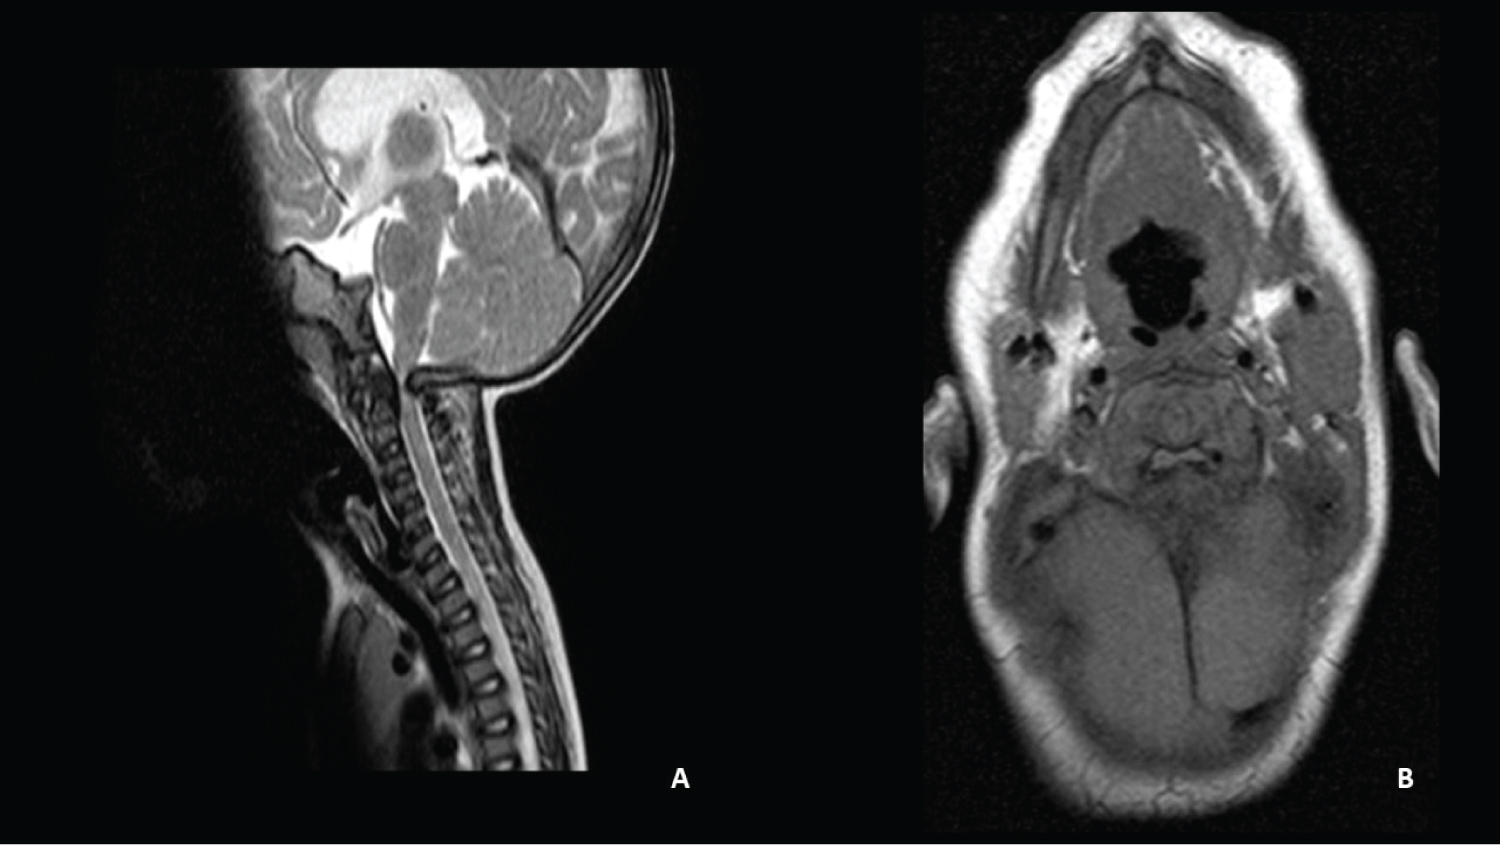

A caucasian male with prenatal diagnosis of AChP was born after a full-term pregnancy from young healthy parents. There was no familiar history of skeletal dysplasia. At four months of age, he was referred to our department after a one-month evolution of cervical hyperextension and failure to thrive, with crossing of two percentile lines downwards in weight and length, at the time growing under the 5th percentile. On neurological examination, he presented opisthotonos, slight quadriparesis, and poor head control. He had no signs of intracranial hypertension. Skeletal X-rays revealed a large cranium, with short base and a small foramen magnum, flat vertebral bodies, small iliac bones, and proximal shortening of long bones. MRI of the craniovertebral junction showed a marked cervicomedullary compression due to foramen magnum stenosis with high signal intensity changes on T2-weighted images as shown in Figure 1.

Figure 1: Patient 1- MRI showing the craniovertebral transition in sagittal (A) Axial; B) Planes. A marked compression in the cervicomedullary transition is observed. View Figure 1